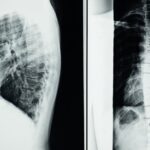

Si vous êtes aux prises avec des douleurs chroniques qui semblent inévitables malgré les traitements traditionnels, il est peut-être temps de considérer une approche différente. La décompression neurovertébrale se révèle être une méthode thérapeutique non invasive qui offre un soulagement significatif pour des pathologies discales sévères telles que la hernie discale, le bombement discal, et bien d’autres. En créant une pression négative à l’intérieur du disque, cette technique permet de réduire la pression sur les nerfs environnants et favorise la circulation sanguine locale, contribuant ainsi à la guérison des tissus endommagés. Pourquoi continuer à endurer des douleurs lorsque une solution efficace est à portée de mains?

En quoi consiste la décompression vertébrale?

Elle consiste à étirer doucement la colonne vertébrale pour créer une pression négative, permettant au disque de se repositionner et de réduire les compressions nerveuses.